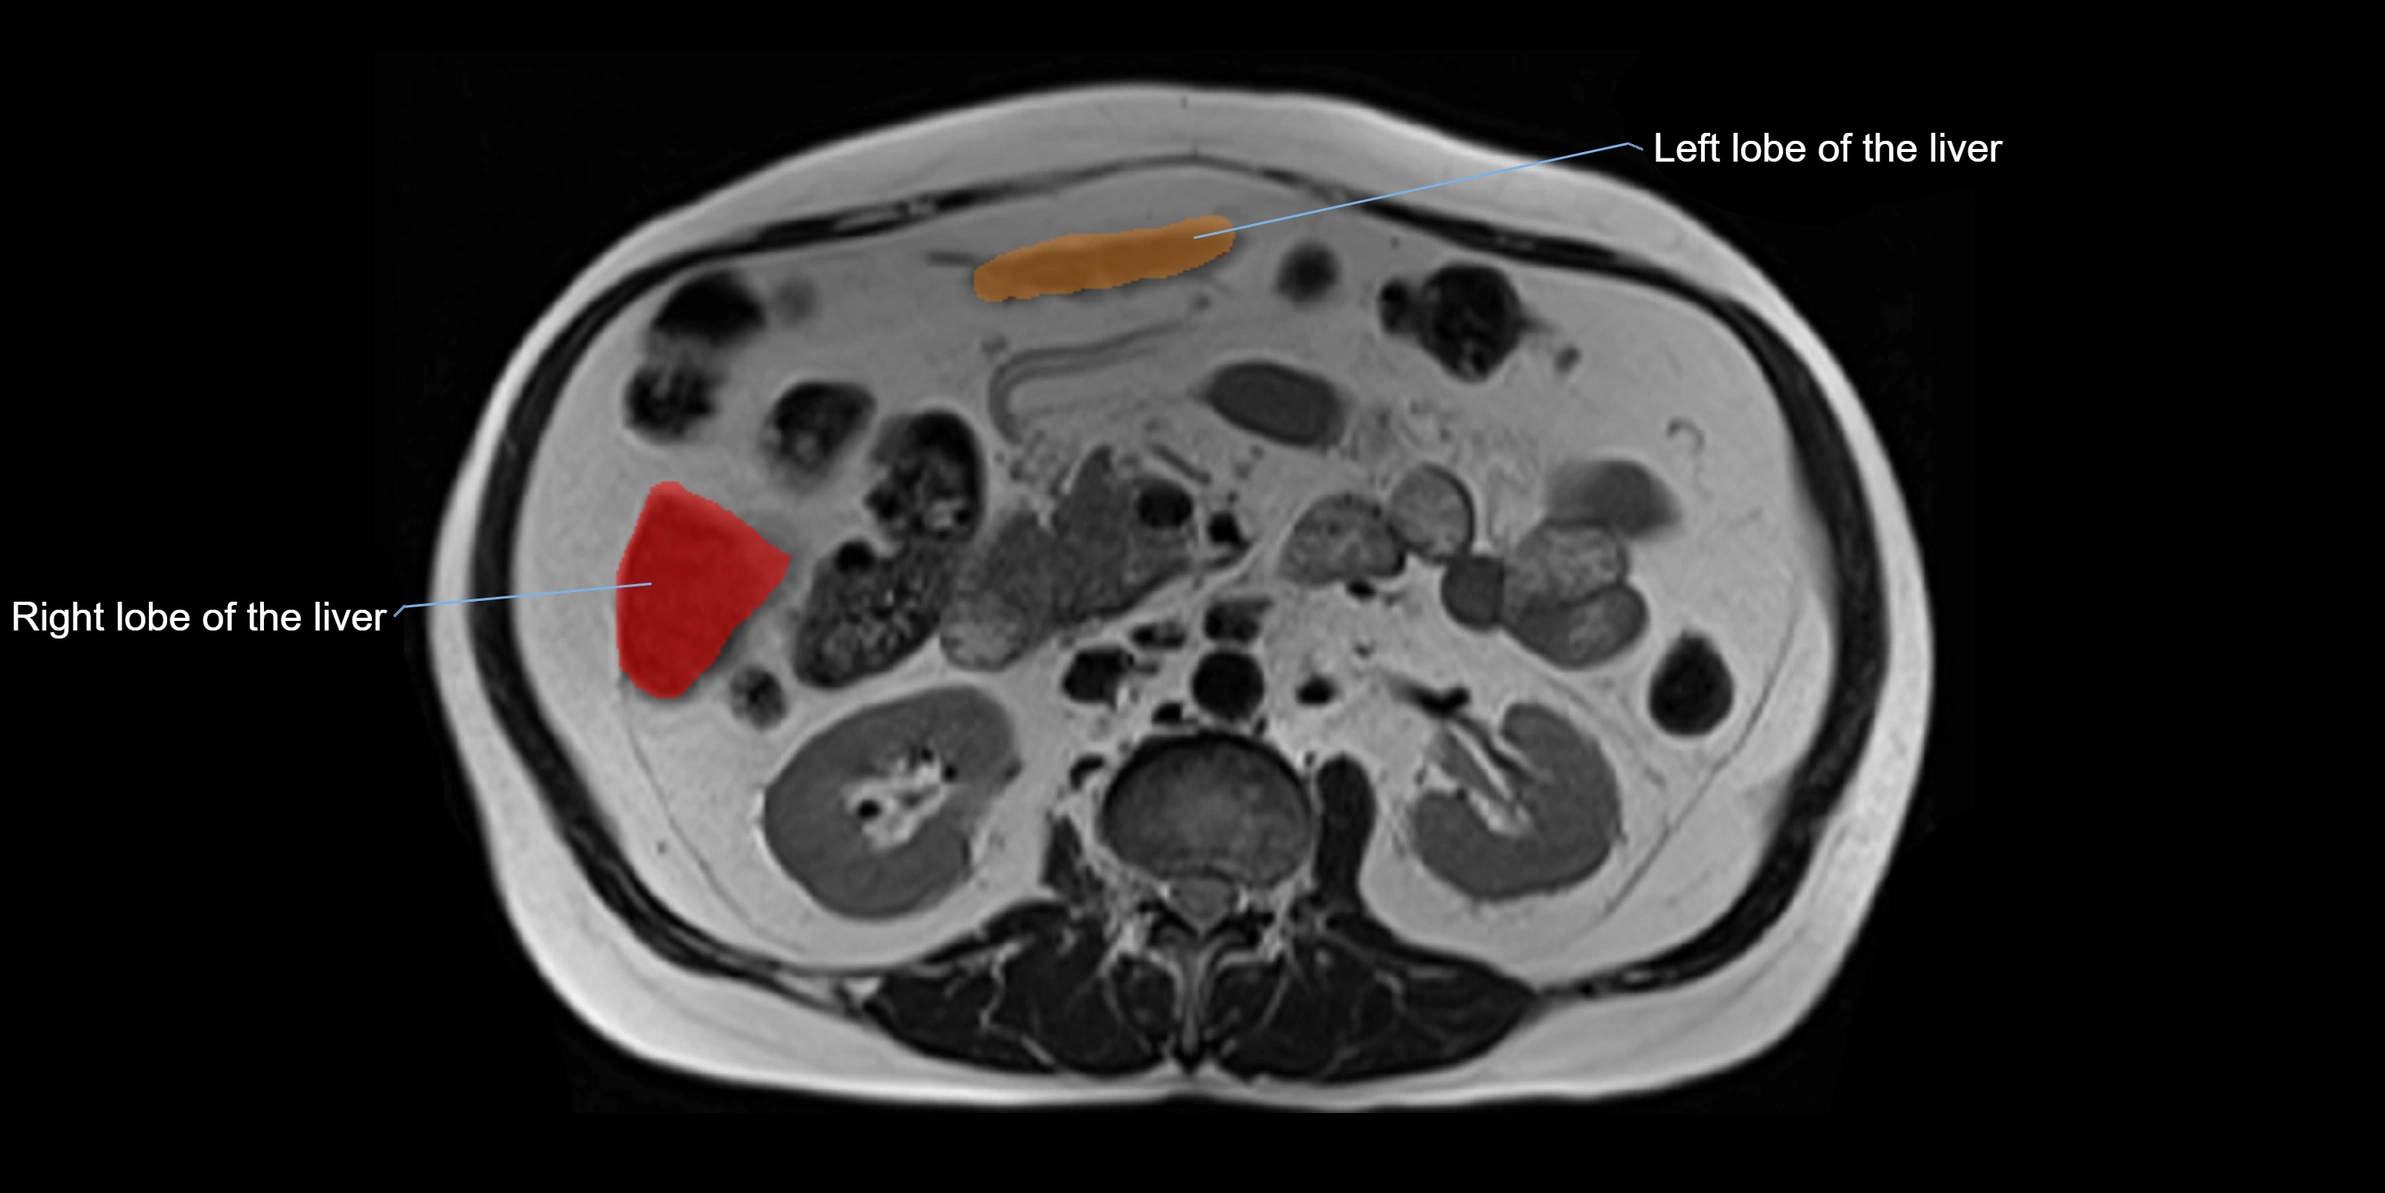

The caudate lobe of the liver is a distinct anatomical subdivision of the liver, designated as segment I in Couinaud’s classification. It lies on the posterior surface of the liver, between the fissure for the ligamentum venosum (left boundary) and the groove for the inferior vena cava (IVC) (right boundary). Superiorly, it is related to the posterior liver surface, and inferiorly it is separated from the left lobe by the porta hepatis.